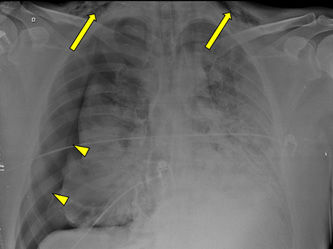

Figure 2: Chest X-ray performed on day 4 of hospitalization, after admission on ICU. The image showed bilateral infiltrative opacities, cervical subcutaneous emphysema (arrows) and signs of pneumomediastinum (arrowheads).

Figure 3A: Chest X-ray performed on admission, which found only extensive bilateral pulmonary opacities.

Figure 3B: Chest X-ray performed on day 4 of hospitalization. The findings include bilateral infiltrative opacities, cervical subcutaneous emphysema (arrow) and signs of pneumomediastinum (arrowheads), the last two which were not present on the previous X-ray.

Figure 4: On day 8, a control chest X-ray performed short after intubation found cervical subcutaneous emphysema (arrows) and a large pneumothorax on the right with subtotal lung collapse (arrowehads), requiring surgical chest tube placement.